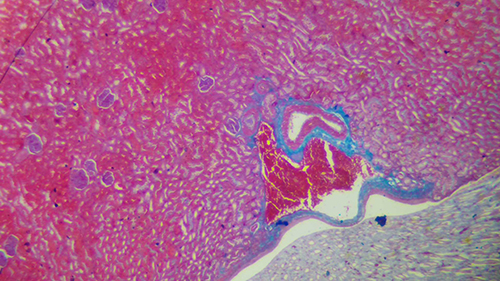

明场,也称为明视场或BF(Brightfield)。它是指成像过程中靠透射光直接成像的方法,如柯勒照明系统。在明场观察中,背景为亮色,而目标物体则呈现为暗色。

明场观察是光学显微镜的基础观察方式,它利用可见光(约400-700nm)作为照明光源,光线相位、照射角度等性质不作改变,直接照射在样品上进行成像。这种观察方式有透射照明和反射照明两种,透射照明适合有透明度的薄样品,而反射照明则适合不透明的厚样品。

明场观察能较好地呈现样品色彩,但衬度较低,尤其是透射照明的明场中。在透射照明成像过程中,带有样品信息的光线与背景光线混合在一起,这使得样品浅色部分与背景的对比度较低,对于活细胞等透明样品,可能难以看出细节。

总而言之,明场是显微镜观察方式中的一种,其特点是通过透射光直接成像,背景为亮色,目标物体为暗色,适用于已经染色或本身有颜色的样品的成像观察。